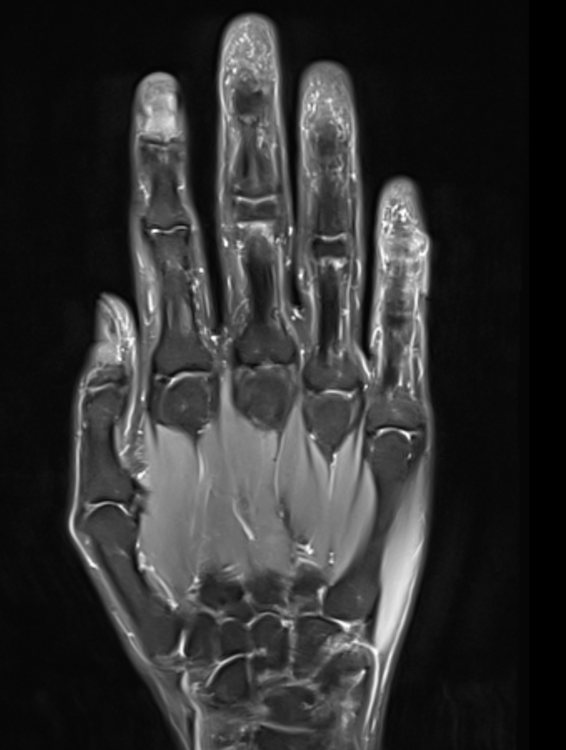

Ich wollte wieder ein Update geben. Und zwar war ich heute Morgen beim Radiologen und habe mir ein privat bezahltes MRT der rechten Hand machen lassen.

Die gute Nachricht ist, dass die Gelenke mit Ausnahme der Endgelenke soweit alle gut aussehen und es keine Wassereinlagerungen usw. gäbe. Was etwas verwunderlich war, ist die Tatsache, dass ich wohl Recht viele Kapilargefäße hätte. Am Zeigefinger ganz deutlich zu sehen, an den anderen Fingern auch vermehrt feststellbar. Dass es am Zeigefinger aufgrund der Psoriasis ist, sei möglich. Die anderen Finger sind ja bei der rechten Hand aber soweit unauffällig, nur dass hier und da vereinzelt die Gelenke zwicken.

Vielleicht ist das in den Gelenken auch eine Überlastung durch die Computerarbeit und vielen Handytippen und erklärt deshalb die Beschwerden.

Trotzdem interessant, wieso die Durchblutung da stärker sei, obwohl meine Finger ja meistens kalt sind 😂

Hier noch die MRT Bilder als Auszug für den interessierten Leser: